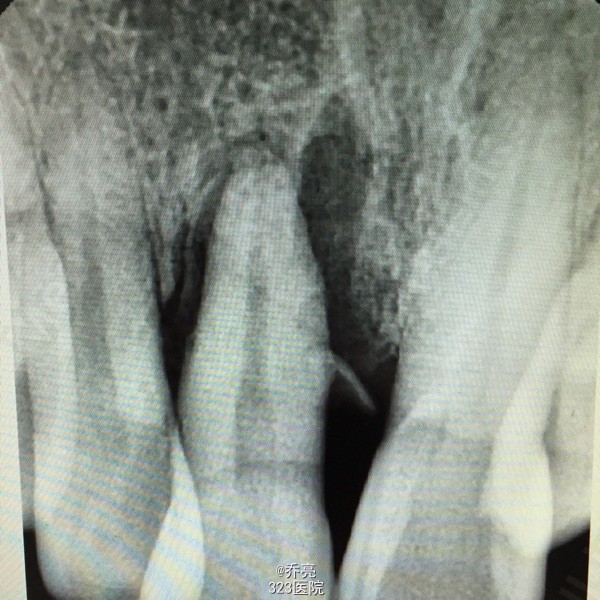

左下后牙金属牙冠松动,牙齿咬物不适一个月

左下7金属牙冠松动,不密合,去除后牙体缺损,面积较大,探(+)冷(+)松动1度,叩(+-) 右上1松动2度 x线示:左下7缺损及髓,根尖无明显异常 右上1根尖阴影

诊断:左下7慢性牙髓炎 右上1牙槽骨吸收 建议:左下7RCT+桩+冠 右上1抜除后修复 处理:左下7清理根管,双氧水冲洗,干燥置木溜油棉,ZOE暂封 右上1局麻下拔除,牙槽窝搔刮,恢复牙槽窝,咬干棉球止血